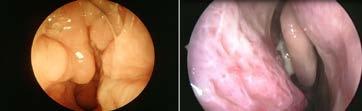

비염일까, 축농증일까…"콧물 색깔 잘 살펴야"

비염과 부비동염(축농증)은 각기 다른 질환이지 만 '콧물'이라는 증상이 유사하다. 두 질환에서 비롯

된 콧물은 답답하고 지긋지긋할 뿐만 아니라 안면부 압박감과 두통까지 유발한다.

하지만 이런 콧물을 가볍게 여기지 말고 세심하 게 살펴볼 필요가 있다. 자칫 부비동염을 비염으로

생각해 방치하면 수술로 치료해야 할 수도 있기 때 문이다.

대한이비인후과학회 소속 전문의들에 따르면 비 염과 부비동염은 콧물이라는 증상이 비슷해 헷갈리

지만, 콧물의 색깔을 유심히 관찰하면 구분할 수 있 다.

우선 비염의 콧물은 맑은 게 특징이다. 여기에 코 막힘과 간지러움, 재채기 등이 동반된다. 원인이 알 레르기에 의한 것이면 알레르기 비염, 그렇지 않으면 비(非) 알레르기 비염으로 구분한다.

알레르기 비염은 환절기의 꽃가루와 동물의 털 등 다양한 원인에 의해 발생한다.